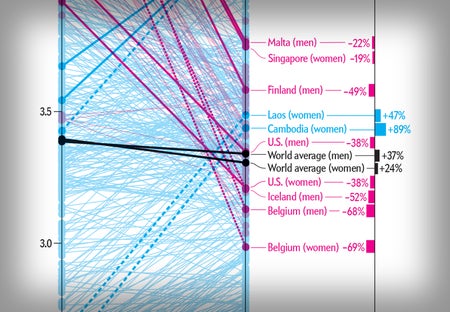

Cholesterol Drops in the West and Rises in the East

Blood levels change as people alter diets and the use of statin medications